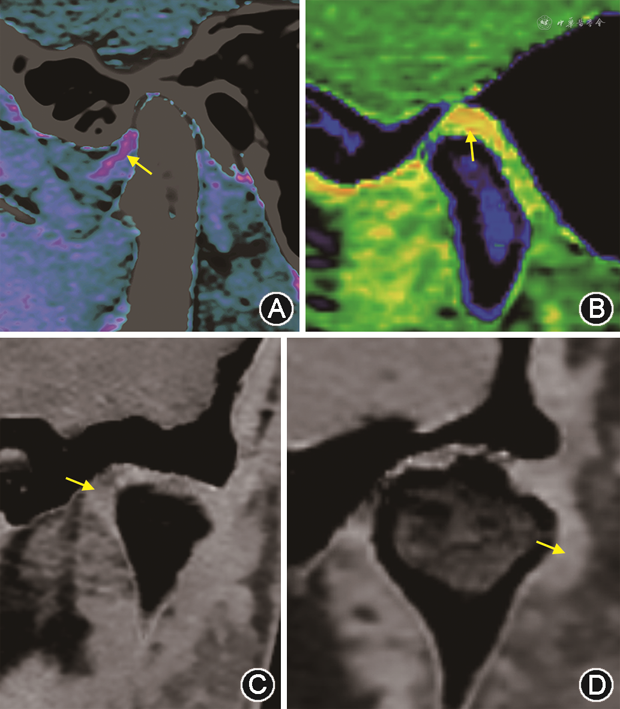

能谱CT为三维螺旋采集数据,后处理时可以将钙抑制图像与原始CT图像进行刚性融合,更清晰直观地显示关节盘的形态及位置(图2)。同时,根据其三维采集特点,可以进行任意角度多平面重建(图3),从不同角度观察关节盘的形态及位置关系。

注:箭头示关节盘

TMD常见的关节盘移位包括前移位、后移位、内侧移位及外侧移位(图4)[5],均可在钙抑制CT成像上清晰显示。

注:箭头示颞下颌关节盘